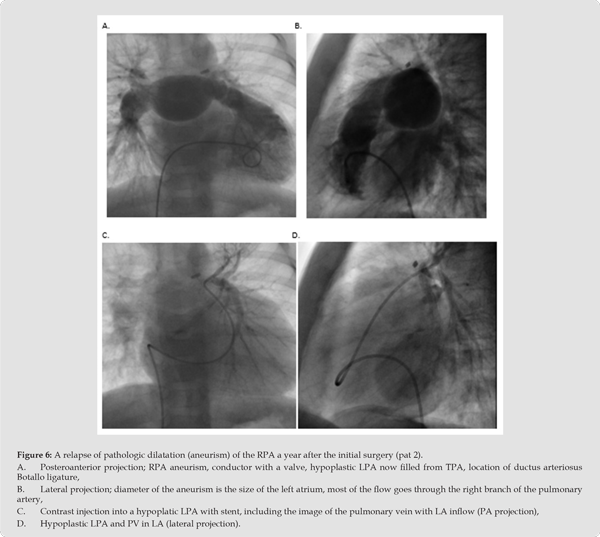

We present four patients with the mentioned entity who were hospitalized in our Clinic in the last 3 years. All four had a foetal cardiac examination, but it seems that the searchers did not always have in mind the possible syndrome we want to present. In one patient, fluid accumulation in the nuchal region (foetal nuchal translucency, FNT) was observed as early as 14 weeks of gestation, but later (22 weeks) only a general suspicion was raised on CHD (Pat. 1). The situation is similar with the second patient (patient 3), in whom a congenital heart defect (CHD) was also suspected at 23 weeks’ gestation, with the addition that it was pulmonary stenosis (PS) with consecutive right ventricular hypertrophy (RVH). This ignores the fact that the previous pregnancy was terminated at 14 weeks’ gestation due to cystic hygroma. In two children (patients 2 and 4), the correct diagnosis was already made prenatally by foetal echocardiography. In both patients, a very wide pulmonary artery trunk (TPA) and the right pulmonary artery branch (RPA) dominated, and the pulmonary valve in both was deficient and manifested as a ridge without the function of opening in systole and closing in diastole, therefore, with stenosis and insufficiency (patient 2) or only with severe insufficiency (patient 4).

Consequently, they had RVH with suspicion of non-compaction right ventricular cardiomyopathy, more so in patient 4 than in patient 2 (Figure 1A-1D. – patient 2 and Figure 2A-2D-patient 4). Anomaly of ductus arteriosus is suspected in both of patients; in patient 2, a small, restrictive anomalous duct, through which only LPA is supplied, and which is separated from TPA (Figure 3A-3D - patient 2), in patient 4 there is an atypical, wide, tortuous arterial duct through which it enters the TPA, and then through the deficient PV into the RV. Massive insufficiency behind the trunk of the pulmonary artery towards the right ventricle is shown, and then the right ventricle with severe non-compaction cardiomyopathy (Figure 4A-4D - patient 4). In the other two patients, the ductus was not noted in the foetal cardiological examination. Interestingly, all pregnant women had problems during pregnancy; two had gestational diabetes mellitus and arterial hypertension, one had foetal hydrops and cystic hygroma (termination of previous pregnancy at 14 weeks), and one had a previous spontaneous abortion of unexplained aetiology. There is no information on any drug therapy during pregnancy.

In the postnatal diagnosis, all patients had dilatation of the right atrium, insufficiency of the tricuspid valve of varying degrees, dilatation and hypertrophy of the right ventricle, and clear changes in the defective pulmonary valve, which was the cause of severe stenosis in three patients (1,2,3), with a gradient of 60-90 mmHg (Figure 1D, patient 1), and all of them simultaneously had severe insufficiency in the same level of degree II-III, and in patient 4 only severe insufficiency dominates without registered stenosis (Figure 2C, pat. 4)). We reliably found pathological DB in three patients (2,3,4), with the fact that one duct was constricted and directed into the hypoplastic left PA that was separated from the right (Pat. 2) (Figure 3B,C & D, Pat. 2) in the frame of the TF type.